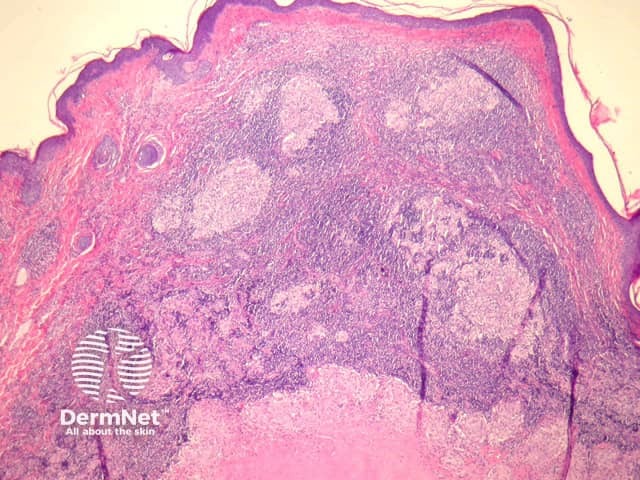

Primary inoculation with tubercle bacilli may begin with surface ulceration, epidermal hyperplasia, and a dense dermal infiltrate rich in neutrophils (figure 1). Disseminated cutaneous tuberculosis and orificial tuberculosis will typically show a similar neutrophilic reaction in early lesions. Over time, the neutrophils are replaced by chronic inflammatory cells and necrotising granulomatous inflammation surrounded by numerous lymphocytes if the patient has a competent immune system (as seen with the clinical subtype tuberculosis verrucosa). Figures 2,3,4 show the same image of the characteristic necrotising granulomatous inflammation surrounded by a lymphocytic response at progressively higher magnifications. Tubercle bacilli are usually easy to find in early suppurative lesions and difficult to identify when the granulomatous inflammation has become well developed.

Lupus vulgaris is the most common clinical type of re-infection cutaneous tuberculosis and shows well-formed granulomas surrounded by chronic inflammatory cells, and central necrosis (figures 2-4). The necrosis is usually less pronounced than the example illustrated here.

Figure 2

Figure 3